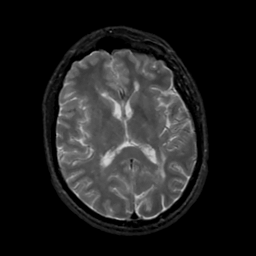

MR Study #5, March 10, 1991 -- Slice #29